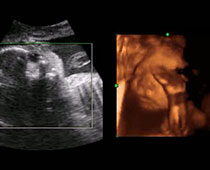

- Fetal Parts Ultrasound Scan Photos

- Second Trimester Ultrasound Photos

- The Clinical Advantages of 3D and 4D Ultrasound

- Definition and Features of Four Dimensional Ultrasound

- Uses of 4D Ultrasound scan